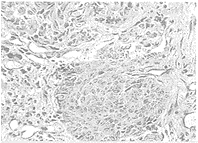

患者男性,33岁,进行性吞咽梗阻一个多月入院。体查发现双锁骨上淋巴结肿大,最大1cm×1cm,质韧,固定,无压痛。食管X线点片:食管胸中段相当于第6~8胸椎右后充盈缺损,粘膜中断,壁硬,扩张度差。纤维胃镜检查:距门齿30cm~35cm处食管前壁溃疡灶,周围隆起,易出血;十二指肠球部前壁2cm×2cm溃疡,降部见散在多发性溃疡。活检病理(汕大医学院125969)示:食管鳞状细胞癌Ⅱ级(图1);十二指肠粘膜慢性炎症,粘膜内见鳞状细胞癌浸润(图2)。食管、十二指肠癌灶病理形态相同。腹部CT:胰头周围、腹主动脉左旁及肠系膜见多个结节状影,拟腹腔,腹膜后淋巴结转移;肝、胆、胰、脾、肾未见异常。

图1 食管鳞状细胞癌HE×100

图2 十二指肠粘膜鳞状细胞癌浸润HE×100